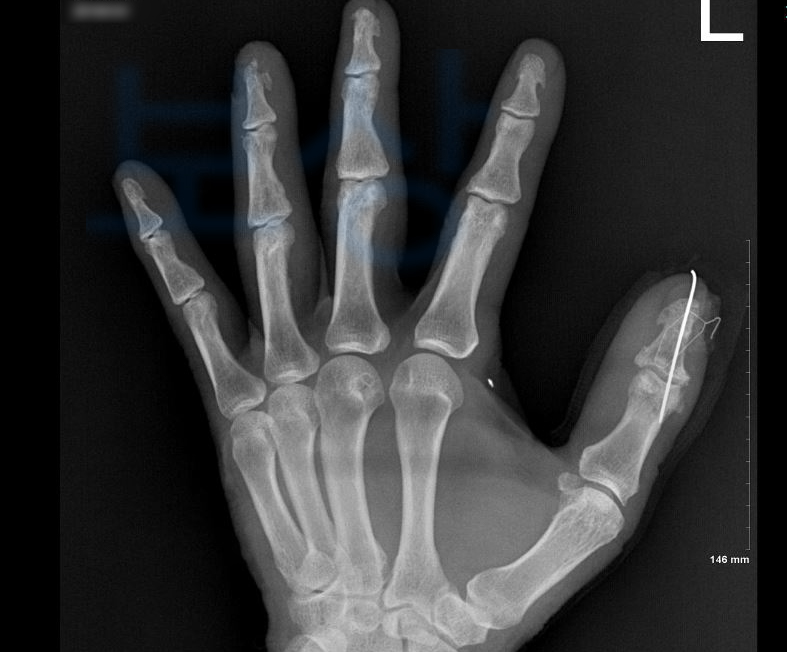

위 재해로 받은 진단은

무지 원위지골 개방성 골절

환지 원위지골 개방성 골절

압궤 손상을 동반한 골절이었죠. 먼저 일하시다 혹은 출퇴근 중 발생한 재해라면 산재보험에서 보상 가능하십니다. 대부분 많은 분들이 회사에서 병원 원무과를 통해 최초 산재신청은 무사히 하십니다.